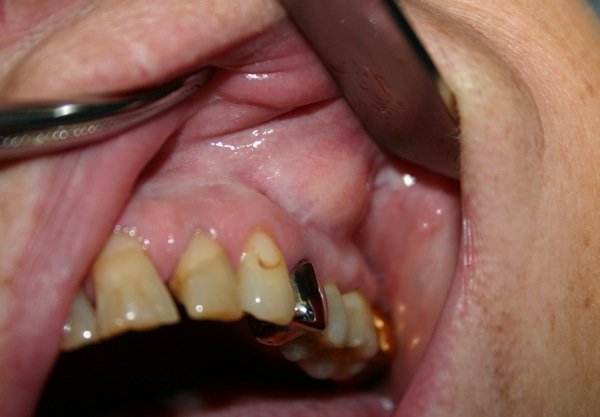

Киста на десне: фото . На фото 1 вы можете увидеть заполненную гноем кисту, которая образовалась в проекции корней разрушенного 6 нижнего зуба . Как выглядит киста на десне у ребенка - фото 2-3 . . .

Киста зуба Фото после извлечения . . . Опухоли на верхней части десны . Киста над зубом — фотоснимок выше — формируется по причине бактериальных заражений или ранений тканей десны .

Киста может принимать совершенно разные размеры, иногда достигая в величину нескольких сантиметров . Возникает это образование на десне, а точнее, в области корней зуба .

Киста зуба - это пузырь, прикреплённый к корню клыка, моляра или резца, заполненный жидкостью, чаще - гноем . Кисты на корнях являются следствием инфицирования и отличаются размерами, расположением и причинами . . .

Киста на рентгеновском снимке — это овальное пятно с четкими контурами (смотрите фото) . По месту локализации наиболее распространены киста зуба мудрости, передних зубов и гайморовой пазухи .